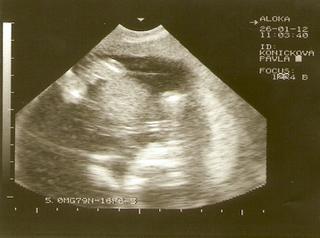

Tak kontrola dopadla v pořádku, ted už můžu být klidná, naposledy jsem byla na UZ v 11+5 a dnes jsem už 16+3 a prcek je v pořádku 🙂 Na fotečce není celá hlavička, protože už je moc velkej, ale podařila se mu alespon tato fotka,nožičky,ručičky a dole hlavička, pěkně sebou zase mrskal 🙂 A byla krásně vidět celá páteř,neskutečné 🙂 Ani nevím,jak je ted veliký,nedalo se to změřit.